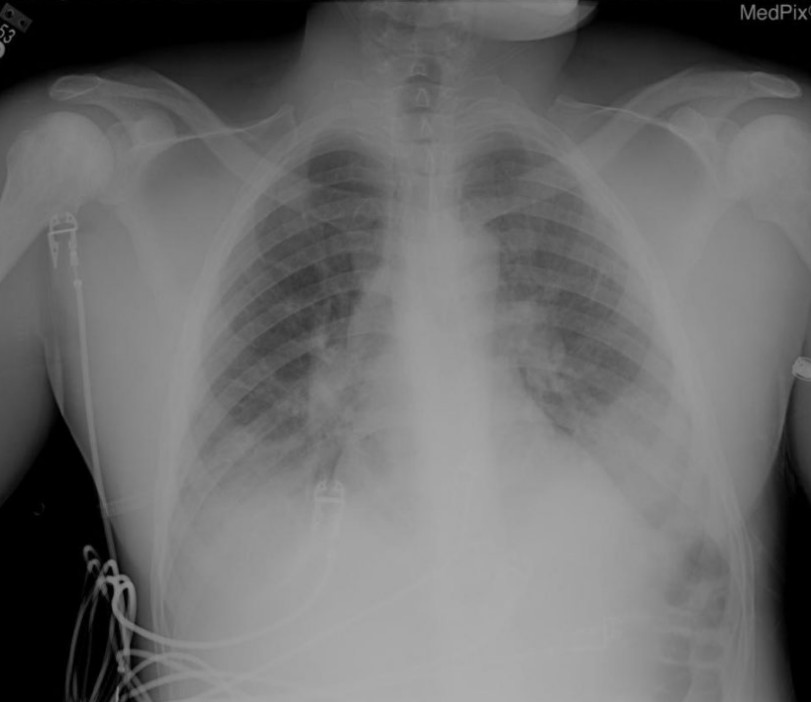

Chest pain in sickle cell disease

A 25-year-old man with sickle cell disease presents with non-productive cough, severe central chest pain and hypoxia. Vitals are as …